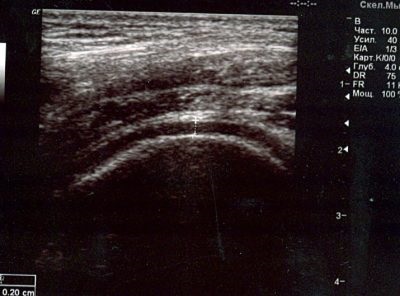

Cu ultrasunete a genunchiului este o metodă de diagnostic importantă, împreună cu examinarea cu raze X si imagistica prin rezonanta magnetica. Această metodă are o serie de avantaje pe care au făcut-o populară în practică ortopedice și traume. Dar, ca orice metodă, cu ultrasunete are anumite limite și capabilități.

Una dintre radiația nu este suficientă pentru diagnostic. Trecerea prin structura de diferite densități acustice, ultrasunete se reflectă. Din unele țesuturi mai mult de la alții mai puțin. Porțiunea reflectată de sunet a înregistrărilor de același senzor pe care le-a generat. Impulsurile primite sunt prelucrate de un software special de calculator și transformată într-o imagine grafică pe masina monitor cu ultrasunete.

Cele mai multe diagnostice sonologov funcționează în ordine strictă, potrivit sondajului de protocol. Inițial, pacientul este pe canapea, culcat cu fața în jos, cu o ușoară curbă la nivelul articulațiilor genunchiului ale picioarelor. Pe zona de studiu este aplicat un gel special, care oferă cel mai apropiat posibil contactul între dispozitivul senzorului și pielea și ajută la minimizarea orice interferență.

Studiul începe în fosa poplitee. În această poziție, cel mai bine este de a examina structurile intra-articulare prin fantă. În această poziție secțiunile din spate sunt investigate meniscul genunchiului. Cercetările arată daune atât meniscului și ligament cruciat intraarticular.

Apoi, pacientul este rugat să se aplece piciorul la articulația genunchiului. Medicul monitorizează unghiul dintre tibia și femurul a fost de aproximativ 50-60 °. Senzorul din nou plasat la nivelul spațiului comun, și, treptat, merge mai departe. În acest caz, încercați să vizualizeze partea din față a departamentelor comune: meniscului anterior și a ligamentului incrucisat anterior, zona patela, saci periarticulare.

Procesul-verbal al ultrasunetelor a indicat un număr mare de indicatori. Multe dintre ele sunt numerice. Aceste cifre permit unei estimări calificate mărimea și distanța dintre structurile individuale, ceea ce este caracteristic leziunilor, boli degenerative și neoplazice.

cavitate comună include în mod normal, un fluid sinovial așa-numita, care lubrifiază suprafețele articulare. genunchi normal de lichid comun cu ultrasunete arata destul de omogen, poate conține o cantitate mică de granule fine.